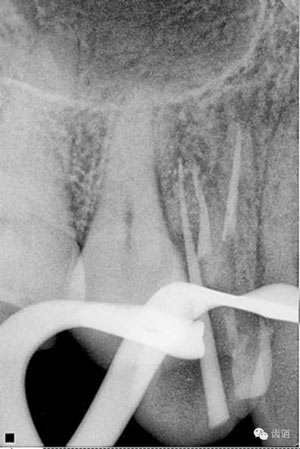

檢查顯示:近頰及腭根充填恰填,遠(yuǎn)頰根管內(nèi)有少許充填物影像。根尖明顯低密度影像。

處理:顯微根管治療。放置橡皮障,去除暫封,顯微鏡下超聲去除頰側(cè)根管上段部分牙本質(zhì),探及遠(yuǎn)中根管口,見有糊劑遮蓋。Path file根管疏通,M Two根管預(yù)備至2506#,配合3%次氯酸鈉和17%EDTA超聲蕩洗,干燥根管,放置氫氧化鈣糊劑,zoe暫封。